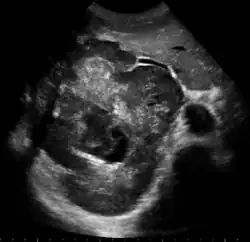

Large HCC filling almost entire of right lobe

Ultrasonography of liver tumors involves two stages: detection and characterization. Tumor detection is based on the performance of the method and should include morphometric information (three axes dimensions, volume) and topographic information (number, location specifying liver segment and lobe/lobes). The specification of these data is important for staging liver tumors and prognosis. Tumor characterization is a complex process based on a sum of criteria leading towards tumor nature definition. Often, other diagnostic procedures, especially interventional ones are no longer necessary. Tumor characterization using the ultrasound method will be based on the following elements: consistency (solid, liquid, mixed), echogenicity, structure appearance (homogeneous or heterogeneous), delineation from adjacent liver parenchyma (capsular, imprecise), elasticity, posterior acoustic enhancement effect, the relation with neighboring organs or structures (displacement, invasion), vasculature (presence and characteristics on Doppler ultrasonography and contrast-enhanced ultrasound (CEUS).